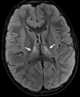

Hypoxic-ischemic encephalopathy

Cerebral hypoxia is a form of hypoxia (reduced supply of oxygen), specifically involving the brain; when the brain is completely deprived of oxygen, it is called cerebral anoxia. There are four categories of cerebral hypoxia; they are, in order of severity: diffuse cerebral hypoxia (DCH), focal cerebral ischemia, cerebral infarction, and global cerebral ischemia. [Source: Wikipedia ]